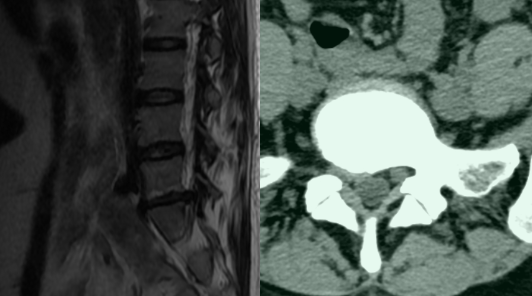

2022年6月17日,岳阳市人民医院钟炯彪主任成功为一名36岁女性腰椎间盘突出患者实施大通道全脊柱内镜下髓核摘除联合纤维环缝合手术,术后患者疗效满意。随着该项技术在院内首次临床上的成功应用,标志着岳阳市人民医院成为岳阳地区开展纤维环修复技术的医院,为岳阳地区脊柱外科发展起到推动作用,同时也为当地广大腰椎间盘突出患者提供了一套更完善的手术治疗方案新选择。

患者术前影像资料,腰五骶一腰椎间盘突出。